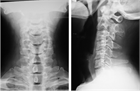

1. 上肢の長時間にわたる同一肢位の継続、反復によって、精神、筋の疲労を背景として発症し、頚椎から肩甲帯に及ぶ筋肉(僧帽筋、胸鎖乳突筋)の疼痛、肩、肩甲骨周囲、腕にかけての痛みやしびれなど頚部、肩、腕、背中を中心としたいわゆる頚肩腕部分の感覚障害が中心となる[1]

1. 痛みやこり感は常在性で、長期間の病期を経過した後に、腕のしびれ、後頭部痛や自律神経症状などが発生するが症状は自覚症状が中心で、神経学的異常所見に乏しい場合に頚肩腕症候群を疑う。